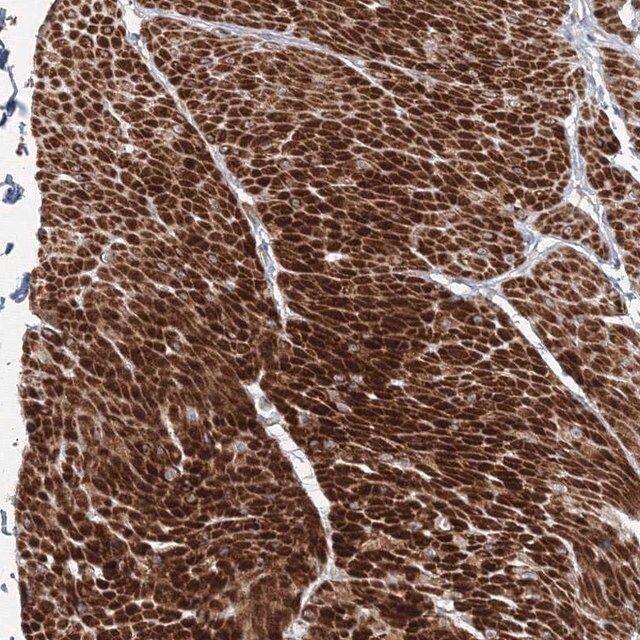

| Application【应用】 | All Prestige Antibodies Powered by Atlas Antibodies are developed and validated by the Human Protein Atlas (HPA) project (www.proteinatlas.org)and as a result, are supported by the most extensive characterization in the industry. The Human Protein Atlas project can be subdivided into three efforts: Human Tissue Atlas, Cancer Atlas, and Human Cell Atlas. The antibodies that have been generated in support of the Tissue and Cancer Atlas projects have been tested by immunohistochemistry against hundreds of normal and disease tissues and through the recent efforts of the Human Cell Atlas project, many have been characterized by immunofluorescence to map the human proteome not only at the tissue level but now at the subcellular level. These images and the collection of this vast data set can be viewed on the Human Protein Atlas (HPA) site by clicking on the Image Gallery link. To view these protocols and other useful information about Prestige Antibodies and the HPA, visit sigma.com/prestige. |

| technique(s) | immunohistochemistry: 1:50- 1:200 |